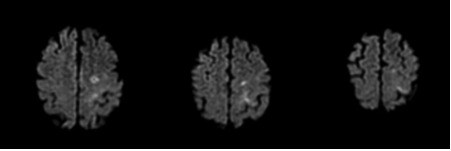

病例2:66岁女性患者,吸烟,既往高血压病史。因突发右侧眼眶周围疼痛、畏光和看到漂浮物而收治入院。头颅CT提示前纵裂SAH。次日DSA未见颅内血管异常,左侧颈内动脉近端可见粥样硬化斑块引起90%以上狭窄。6小时后,患者突然出现失语,头颅MRI-DWI图像显示左侧大脑中动脉供血区多发弥散受限病灶,提示左侧颈内动脉斑块脱落引起的继发性血栓栓塞。患者给予口服阿司匹林治疗,次日行左侧颈动脉内膜剥脱术,术后患者恢复顺利。

图2. A、B. 头颅CT示前纵裂局灶性SAH,大脑前动脉动脉瘤可疑;C-F. DSA显示左颈内动脉近端粥样硬化所致高度狭窄(C),但未发现颅内动脉瘤和血管畸形(D-F);下面两排图像为头颅MRI-DWI相,示左大脑中动脉供血区多发弥散受限病灶。